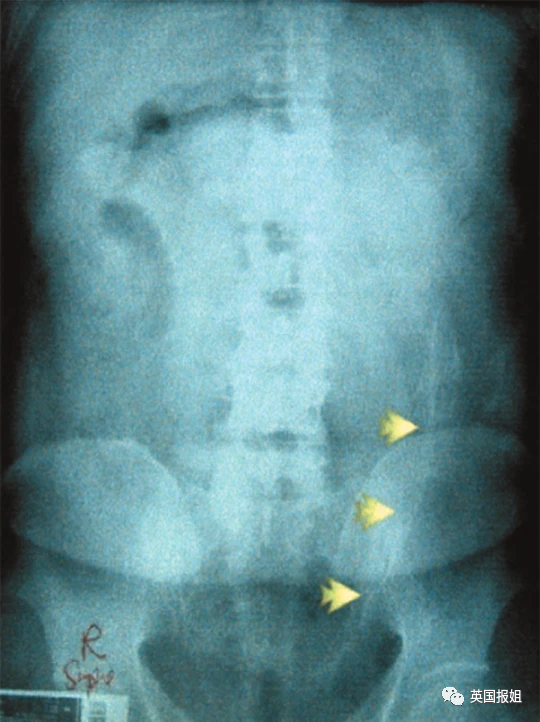

图中的患者是一名72岁的老翁,他自称在上厕所时不慎跌倒在了一个倒着的酒瓶上:

去年印度某医院急诊部闯入一名醉汉,该男子手拎着一根水管子,水管的另一头通向他的屁股。

拍完X光后,当天的值班医生和工作人员都惊呆了,男子竟然将一整个水龙头塞进了后面...